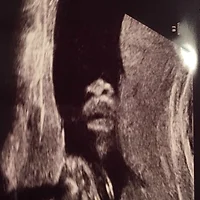

16주차에 방문하던 이날은, 초음파실 들어가기 전에 너무 긴장한 나머지 헛구역질이 날 지경이었다..

그런 내 상태를 알았던 것인지, 선생님이 초음파 한번 볼까요 하고 내 배에 대는 순간

어머, 아들이네요!

너무 선명하게 포착된 다리 사이의 미사일..ㅠㅠ 흐하하..

혹시라도 성별 불확실할까봐 걱정말라는 건지 대놓고 당당하게 보여준다 ㅋㅋ